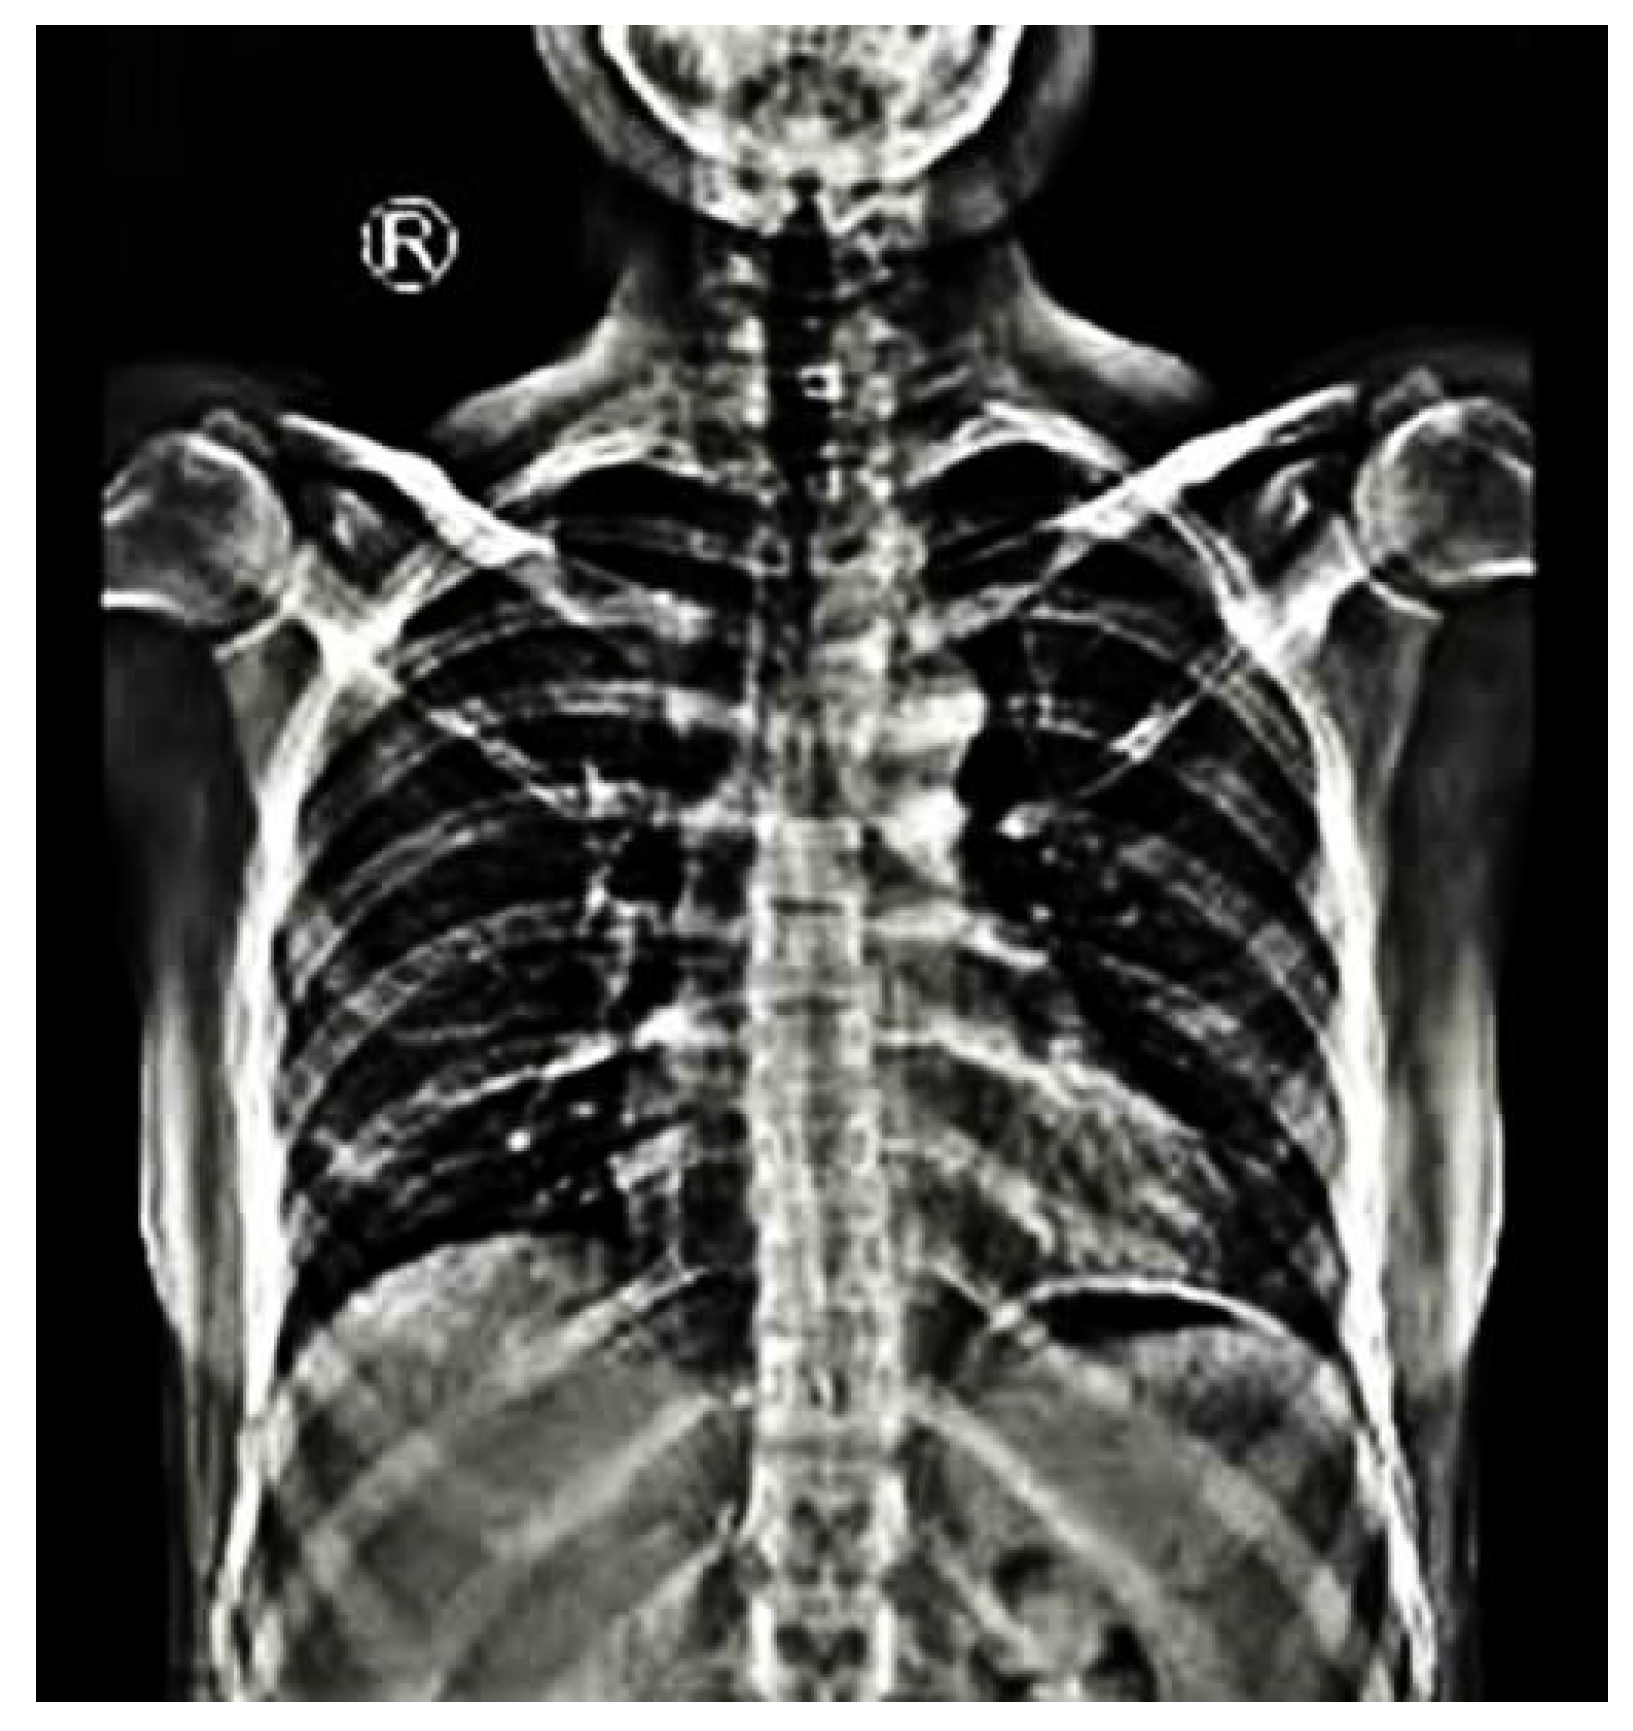

Predicated on the location of the apical vertebrae, scoliosis in NF1 can be classified in two main categories: non-dystrophic and dystrophic. The non-dystrophic scoliotic curves show radiological signs similar to adolescent idiopathic scoliosis (Figure 1) and can aggressively progress to the dystrophic phenotype [30]. Contrariwise, dystrophic malformations develop earlier than non-dystrophic, having a characteristic radiological appearance of sharp and angular curves with severe apical rotation that affect four to six vertebras [30]. The definition criteria of dystrophic scoliosis are presented in detail in Table 1.

Figure 1.

An anteroposterior view of total spine in standing position of a 30-year-old female patient with NF1 demonstrates a right thoracic curve of 12 degrees between 5th and 10th thoracic vertebras without signs of dystrophic malformations. (R: Right).